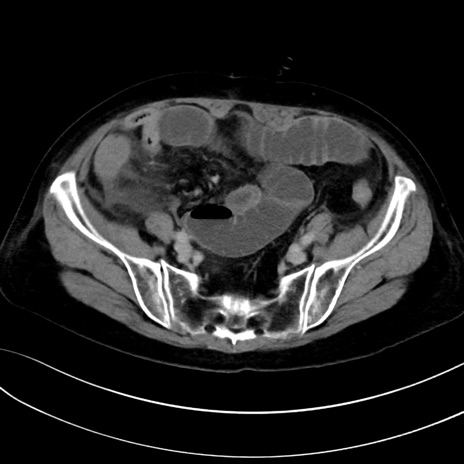

症例13 CT(横断像)1日半後